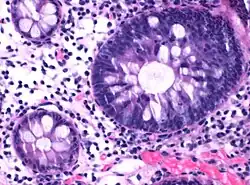

| Micrograph of hyperplastic polyp | |

Histopathologically, there are two main types of hyperplastic polyps, which have genetic differences, as well as different histologic structure, but no significant differences clinically.[4] The two main types of hyperplastic polyps are microvesicular mucin-rich type and goblet cell-rich type.[1] A mucin-poor type with eosinophilic cytoplasm, which is rare, was previously described.[4] However, the mucin poor type is no longer considered a distinct subtype.[1]

Mucin-rich type

The luminal portion has a serrated ("saw tooth") appearance formed by tufts or folds of abundant apical cytoplasm. It contains glands with star-shaped lumina.[4] There are crypts that are elongated but straight, narrow and hyperchromatic at the base. All crypts reach to the muscularis mucosae.[4] The basement membrane is frequently thickened.[4]

Goblet cell-rich type

Elongated, fat crypts and little to no serration. Therefore, they may not be obvious without comparing to adjacent normal intestinal wall.[4]

They are filled with goblet cells, extending to surface, which commonly has a tufted appearance.[4]